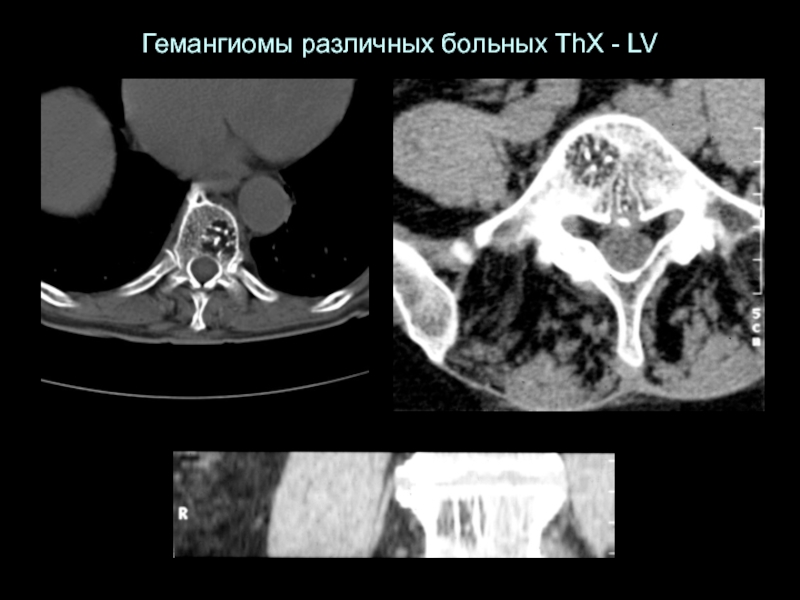

Слайд 25Гемангиомы различных больных ThX - LV

Гемангиомы различных больных ThX - LV